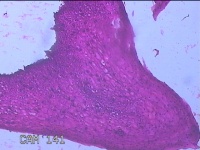

性别年龄35岁临床诊断人乳头瘤病毒感染,宫颈上皮内肿瘤,贫血

一般病史HPV12种亚型(+),TCT低级别病变。阴道镜见醋白薄层,碘着色。

标本名称宫颈3点、7点、9点、12点组织

大体所见1.“宫颈3点组织”:灰白粉红色组织0.7x0.5x0.2cm两块。 2.“宫颈7点组织”:灰白粉红色组织0.7x0.5x0.2cm一块。 3.“宫颈9点组织”:灰白粉红色组织0.5x0.3x0.2cm一块。 4.“宫颈12点组织”:灰白粉红色组织0.8x0.7x0.2cm两块。